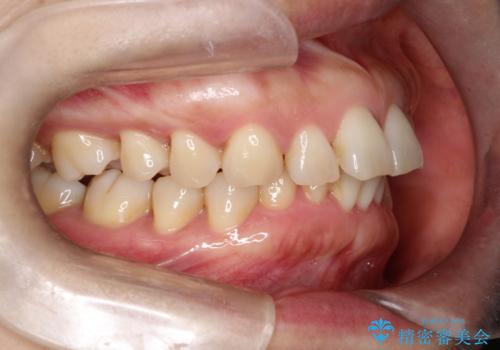

- 前歯が出ていることを主訴に来院されました。

インビザラインにて臼歯部の遠心移動及びIPRを行なっています。

叢生量が多いケースでしたが、綺麗な歯並びとなり患者様にも満足していただきました。

非抜歯矯正のため口元の変化はありません。